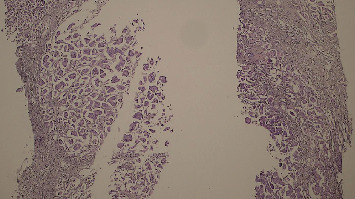

多发原发恶性肿瘤(MPMNs)是指同一个体出现两个或多个不同的肿瘤。同时发生的乳腺癌和结肠癌并不常见,由于缺乏标准化的指南,这给管理带来了挑战。我们报告一位73岁的女性右乳肿块,随后被诊断为2级浸润性导管癌。CT偶然发现右结肠壁增厚,结肠镜活检证实为中分化浸润性腺癌。在新辅助化疗后,她同时接受了根治性乳房切除术、腋窝淋巴结清扫术和右半结肠切除术。术后恢复顺利。辅助放化疗是根据多学科小组(MDT)建议进行的。同步乳腺癌和结肠癌对诊断和治疗计划提出了独特的挑战。MDT合作对于这些复杂病例的个性化治疗策略和优化结果至关重要。

Multiple primary malignant neoplasms (MPMNs) are defined as two or more distinct tumors in the same individual. Synchronous breast and colon cancers are infrequent and present management challenges due to the lack of standardized guidelines. We report a 73-year-old woman presenting with a right breast mass, subsequently diagnosed as Grade 2 invasive ductal carcinoma. Staging CT incidentally revealed right colon wall thickening, and colonoscopy with biopsy confirmed moderately differentiated invasive adenocarcinoma. Following neoadjuvant chemotherapy, she underwent simultaneous radical mastectomy with axillary lymph node dissection and right hemicolectomy. Postoperative recovery was uneventful. Adjuvant chemoradiation was administered per multidisciplinary team (MDT) recommendation. Synchronous breast and colon cancers pose unique diagnostic and treatment planning challenges. MDT collaboration is crucial for personalized treatment strategies and optimized outcomes in these complex cases.